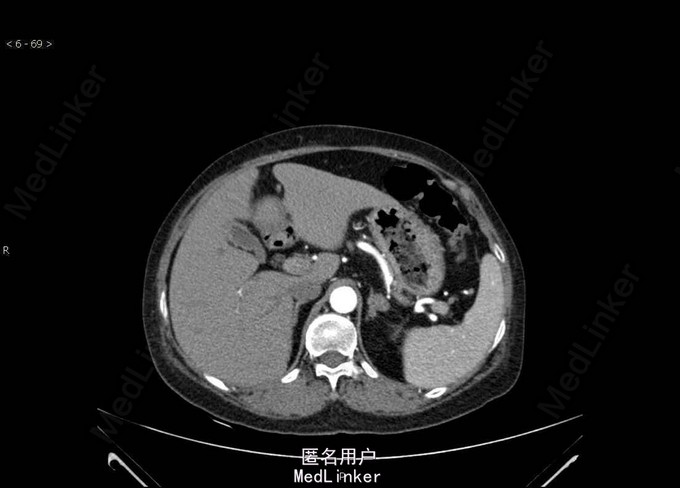

Bp:168/112mmHg,其余无特殊。 肾上腺CT:左侧肾上腺结节,考虑腺瘤可能性大。双肾、脾脏多发囊肿。双肾动脉CTA检查未见明确病变。左侧肾上腺见一大小约25mm×22mm的结节影,CT值约40HU,增强扫描可见强化。右侧肾上腺大小、形态及密度未见明确异常。 术后病理示肾上腺皮质腺瘤。